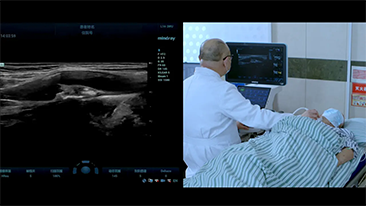

Covid-19?: mise Ă l'ĂŠpreuve des personnels et des dispositifs

L'ÊpidÊmie de coronavirus a forcÊ les h?pitaux et le personnel hospitalier à repenser leurs pratiques de travail, qui impliquent dÊsormais, pendant les pÊriodes aigu?s de crise, la distanciation physique, une utilisation stricte des Êquipements de protection individuelle (EPI), le lavage des mains et la dÊsinfection quotidienne des Êquipements. Les Êquipements hautement mobiles et polyvalents occupent dorÊnavant le devant de la scène dans les environnements cliniques, notamment lorsque les services et salles d'opÊration sont dissÊminÊs sur diffÊrents Êtages et que l'accès à des dispositifs spÊcialisÊs est très demandÊ.